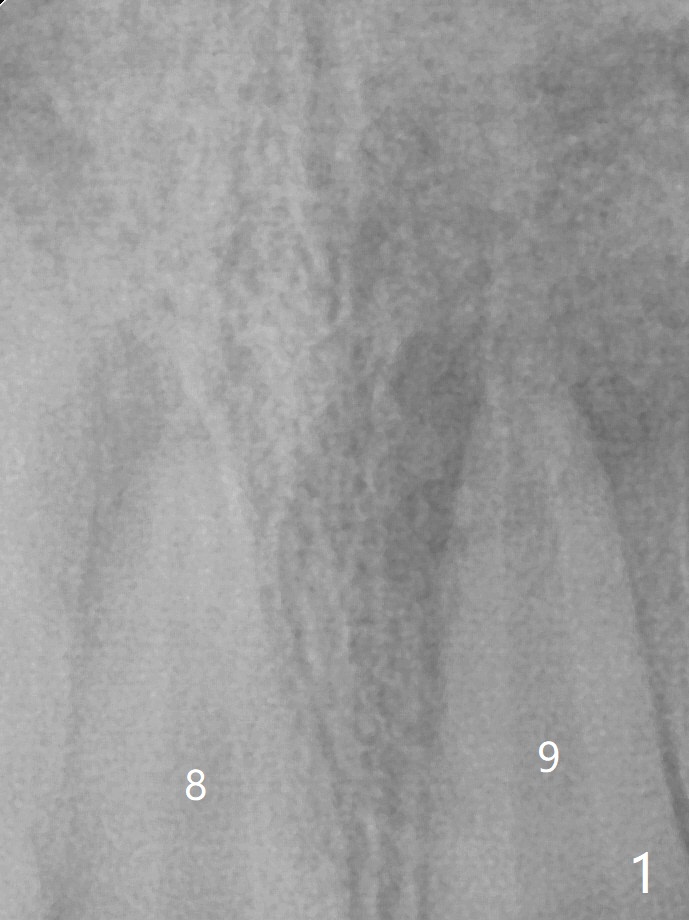

放大后,8号牙根管在根尖处似乎钙化(图一,二(箭头))。图二在图一后1年9个月拍摄。都有根尖阴影,触痛。